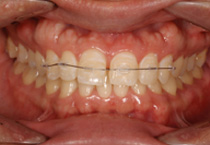

Clear Mini Bracket - Cases

Anterior Crossbite

clear ceramic orthodontic brackets on teeth